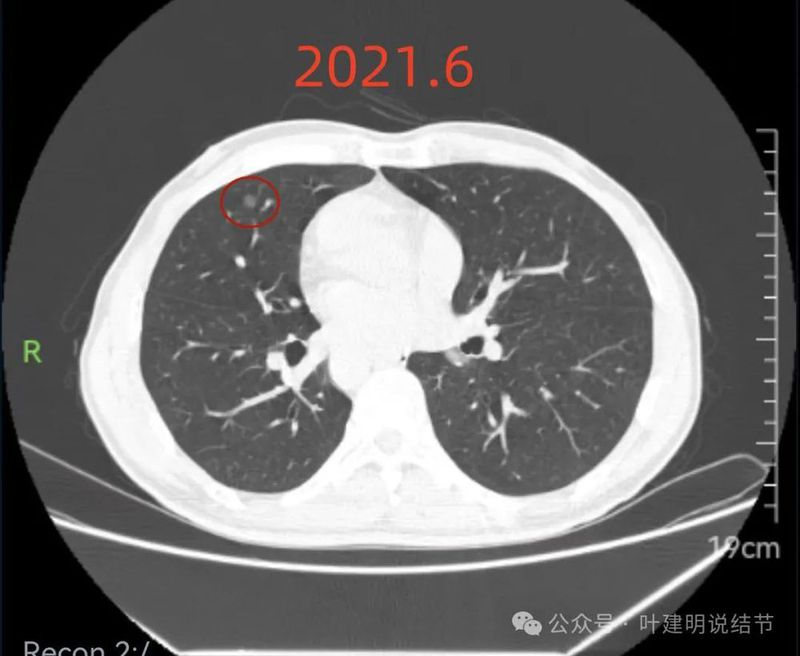

2021年6月右中叶病灶,较前无明显变化。